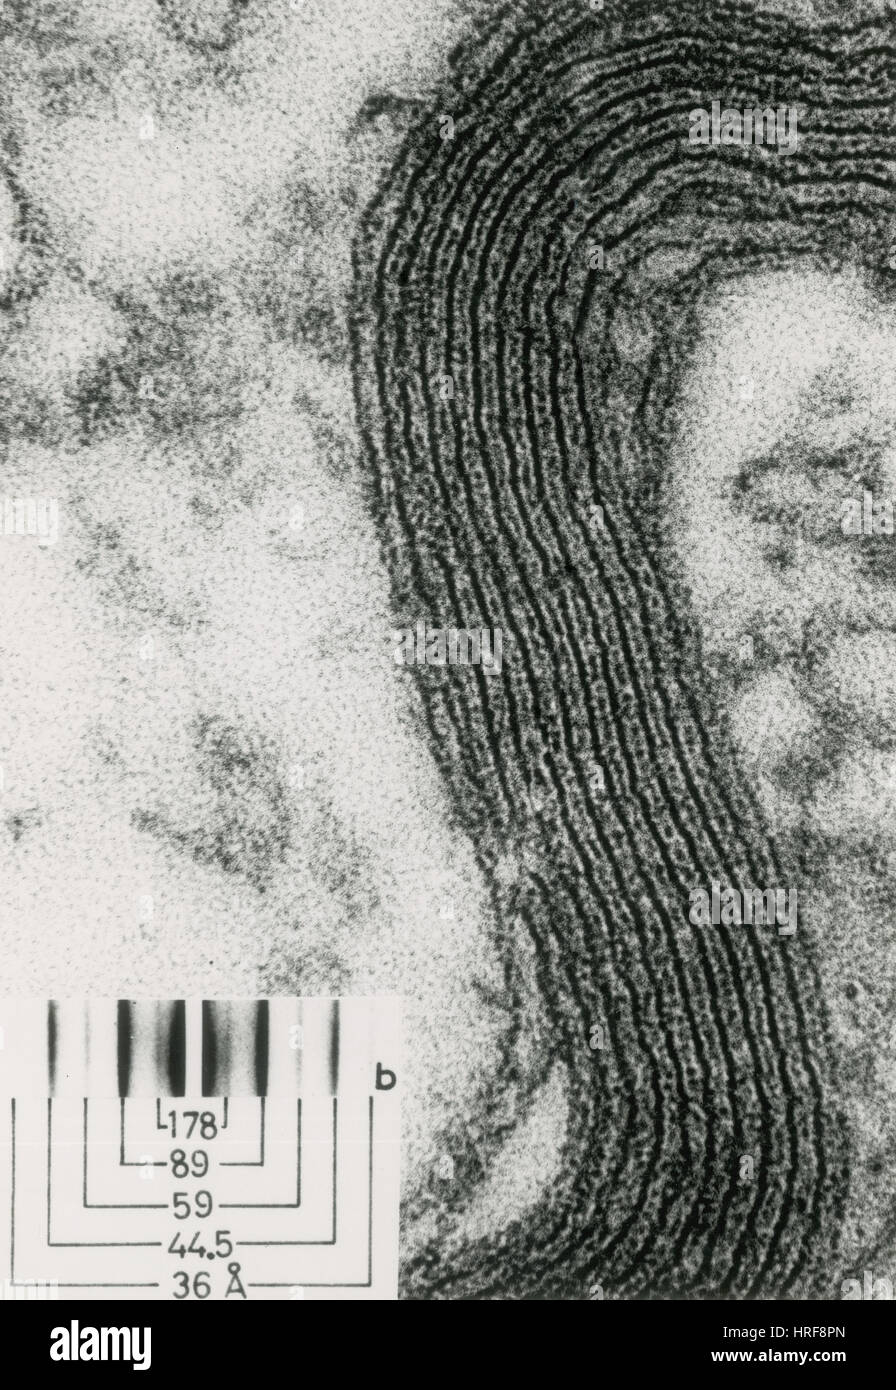

Gaine de myéline, nerf sciatique de grenouille, EM Banque D'Imageshttps://www.alamyimages.fr/image-license-details/?v=1https://www.alamyimages.fr/photo-image-gaine-de-myeline-nerf-sciatique-de-grenouille-em-134945853.html

Gaine de myéline, nerf sciatique de grenouille, EM Banque D'Imageshttps://www.alamyimages.fr/image-license-details/?v=1https://www.alamyimages.fr/photo-image-gaine-de-myeline-nerf-sciatique-de-grenouille-em-134945853.htmlRMHRF8PN–Gaine de myéline, nerf sciatique de grenouille, EM